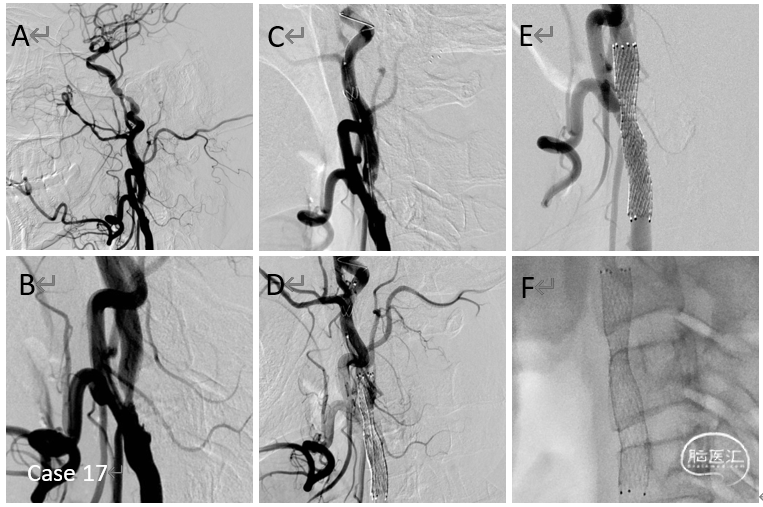

病例17

颈内动脉起始部重度狭窄球囊扩张支架植入术

病例18

后交通动脉瘤复发再治疗